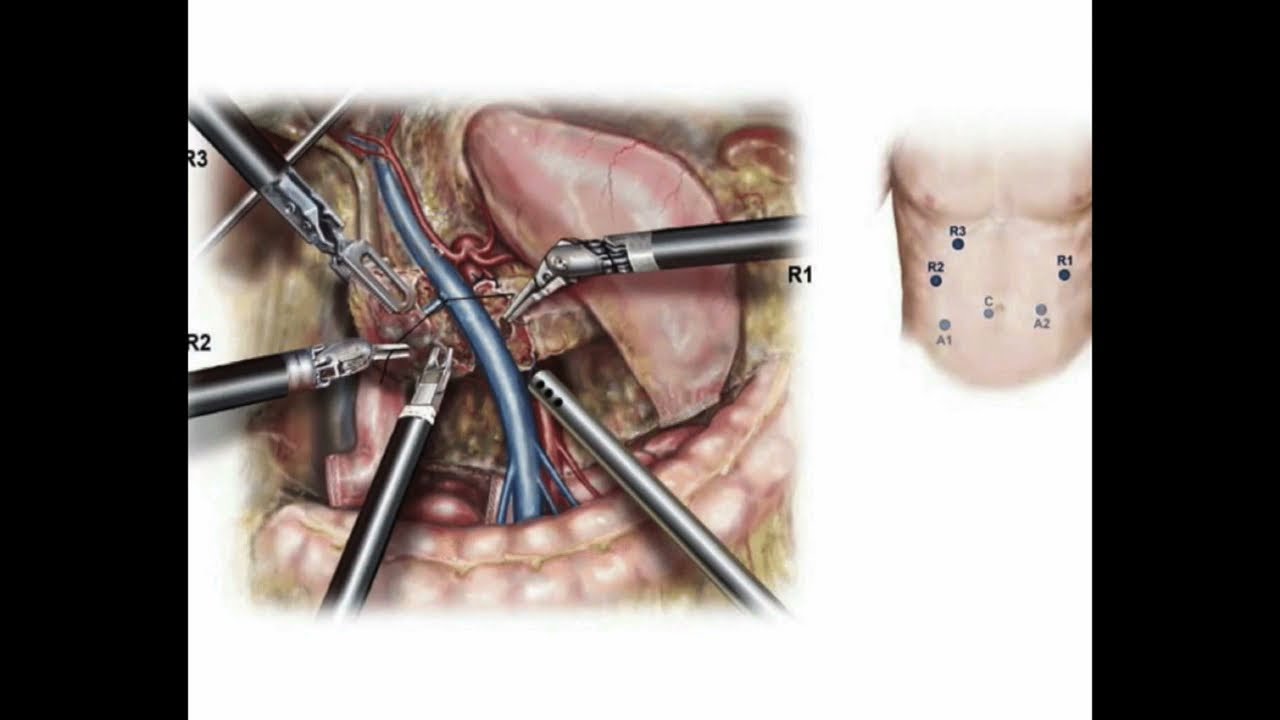

Robotic Total Pelvic Exenteration for Advanced Rectal Cancer

Robotic Total Pelvic Exenteration for Locally Advanced Rectal Cancer

Oncology, Robotics ';